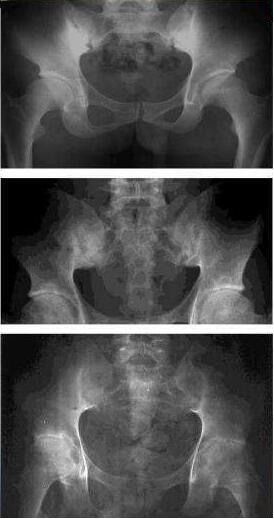

(圖:強(qiáng)直性脊柱炎隨著病情發(fā)展,關(guān)節(jié)會(huì)逐漸畸形)